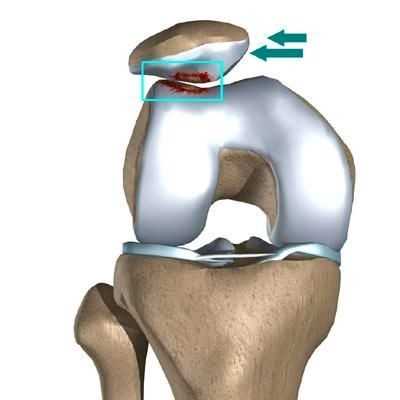

Латеральный вывих надколенника характеризуется разрывом медиального ретинакулюма (медиальной пателло-феморальной связки) коленного сустава. Повторный вывих у пациента — главный признак не выполнения медиальной пателло-феморальной связкой своих функций из-за перерастяжения после первичной травмы.

Вывих надколенника, как первичный, так и повторный, ведет к значимому повреждению хрящевого покрова. Как результат — появляется стойкий болевой синдром и снижение физической активности пациента.

Часто предпосылкой к формированию латеральной нестабильности надколенника становится дисплазия феморопателлярного отдела — врожденного состояния, характеризующегося нарушениями соотношений между надколенником и недостаточно выраженной межмыщелковой бороздой бедренной кости (см. рис.).

Наличие дисплазии различной степени выраженности ведет к тому, что движения надколенника при сгибании и разгибании в коленном суставе происходят с тенденцией к его латеральному смещению. При дополнительном травматическом воздействии это приводит к возникновению полноценного вывиха.